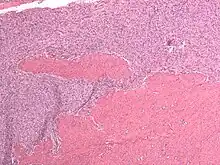

Endometrial stromal sarcoma (low-grade)

Microscopy

- Monotonous ovoid cells to spindly cells with minimal cytoplasm.

- Prominent arterioles. Angiolymphatic invasion common.

- Up to 10-15 mitotic figures per 10 HPF in most active areas.

- Tongue-like infiltration between muscle bundles of myometrium.

- May exhibit myxoid, epithelioid and fibrous change.

- May have foam cells or hyalinization in the stroma.